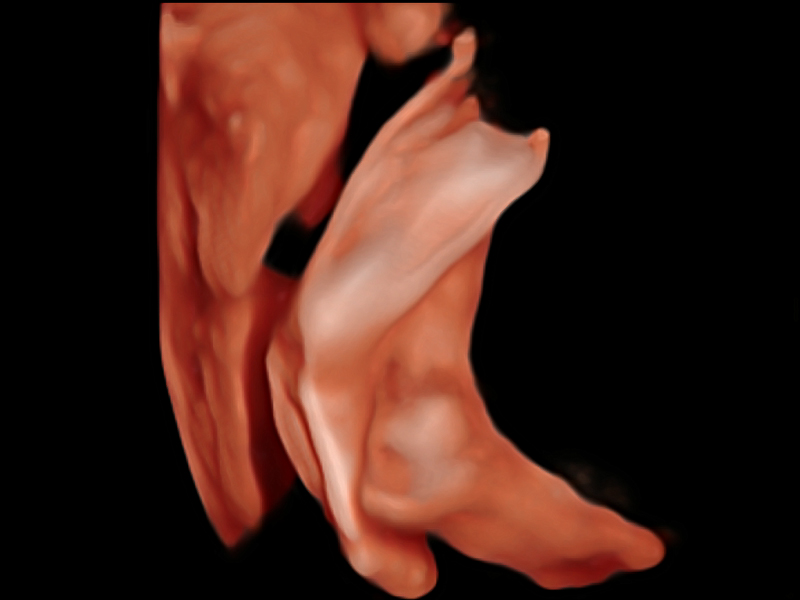

S-Fetus基于大數據深度學習算法,能夠幫助您在產前篩查過程中智能識別胎兒標準切面、自動測量并錄入報告。一個按鍵,即可智能、精準、高效地獲取胎兒生理指標,極大簡化您的產科檢查操作。

可快速對產科掃查切面完成胎兒生理學參數的自動測量,減少操作者按鍵次數,大幅提升檢查效率。

自動識別頸項透明層并獲得NT值,為早孕胎兒畸形篩查提供有效測量工具,提高診斷效率和診斷信心。